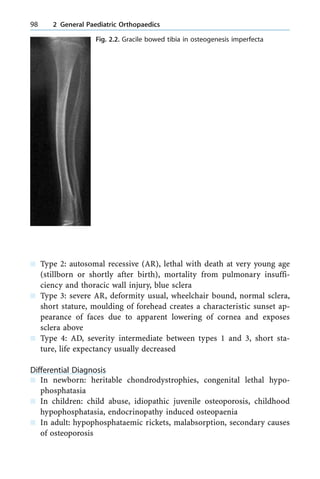

Tensor fascia lata see TFL

Teratogen 373

Teratological dislocation 159

Teres Major 259, 260

Terry Thomas sign 242